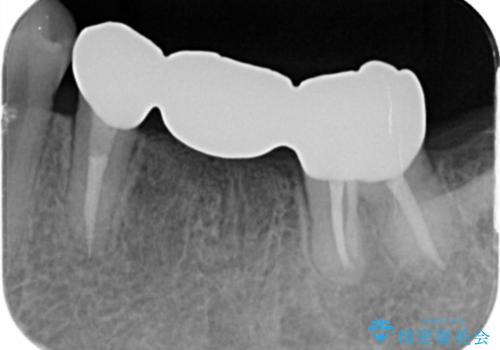

左下6番は残根状態だったため、やむなく抜歯を行い、⑤6⑦ブリッジとしました。

歯周外科手術を併用し、骨の高さを調整して歯の高さをしっかり出す手術(クラウンレングスニング)も行いました。

- 74.8万円(左下567歯周外科手術 15万円、左下⑤6⑦ブリッジ ジルコニアクラウン11万円×3本 仮歯1万円×3本 左下7 精密根管再治療15万円×1 ファイバーコア2万円×2)費用は治療当時の料金となります

左下7番(一番奥)の歯の根管治療は横浜桜木町歯科院長大元が担当しています。

左下5番の根管治療は井上が担当しました。